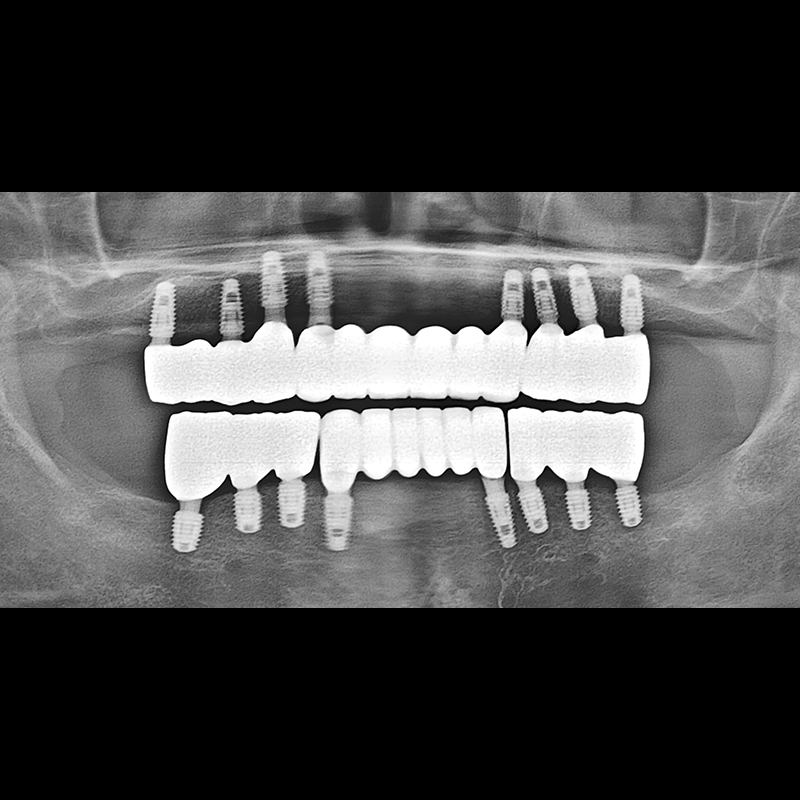

BEFORE AFTER

Implant before and after 2025.05.30

Implants were placed in the missing tooth and in the tooth position where it was difficult to save.